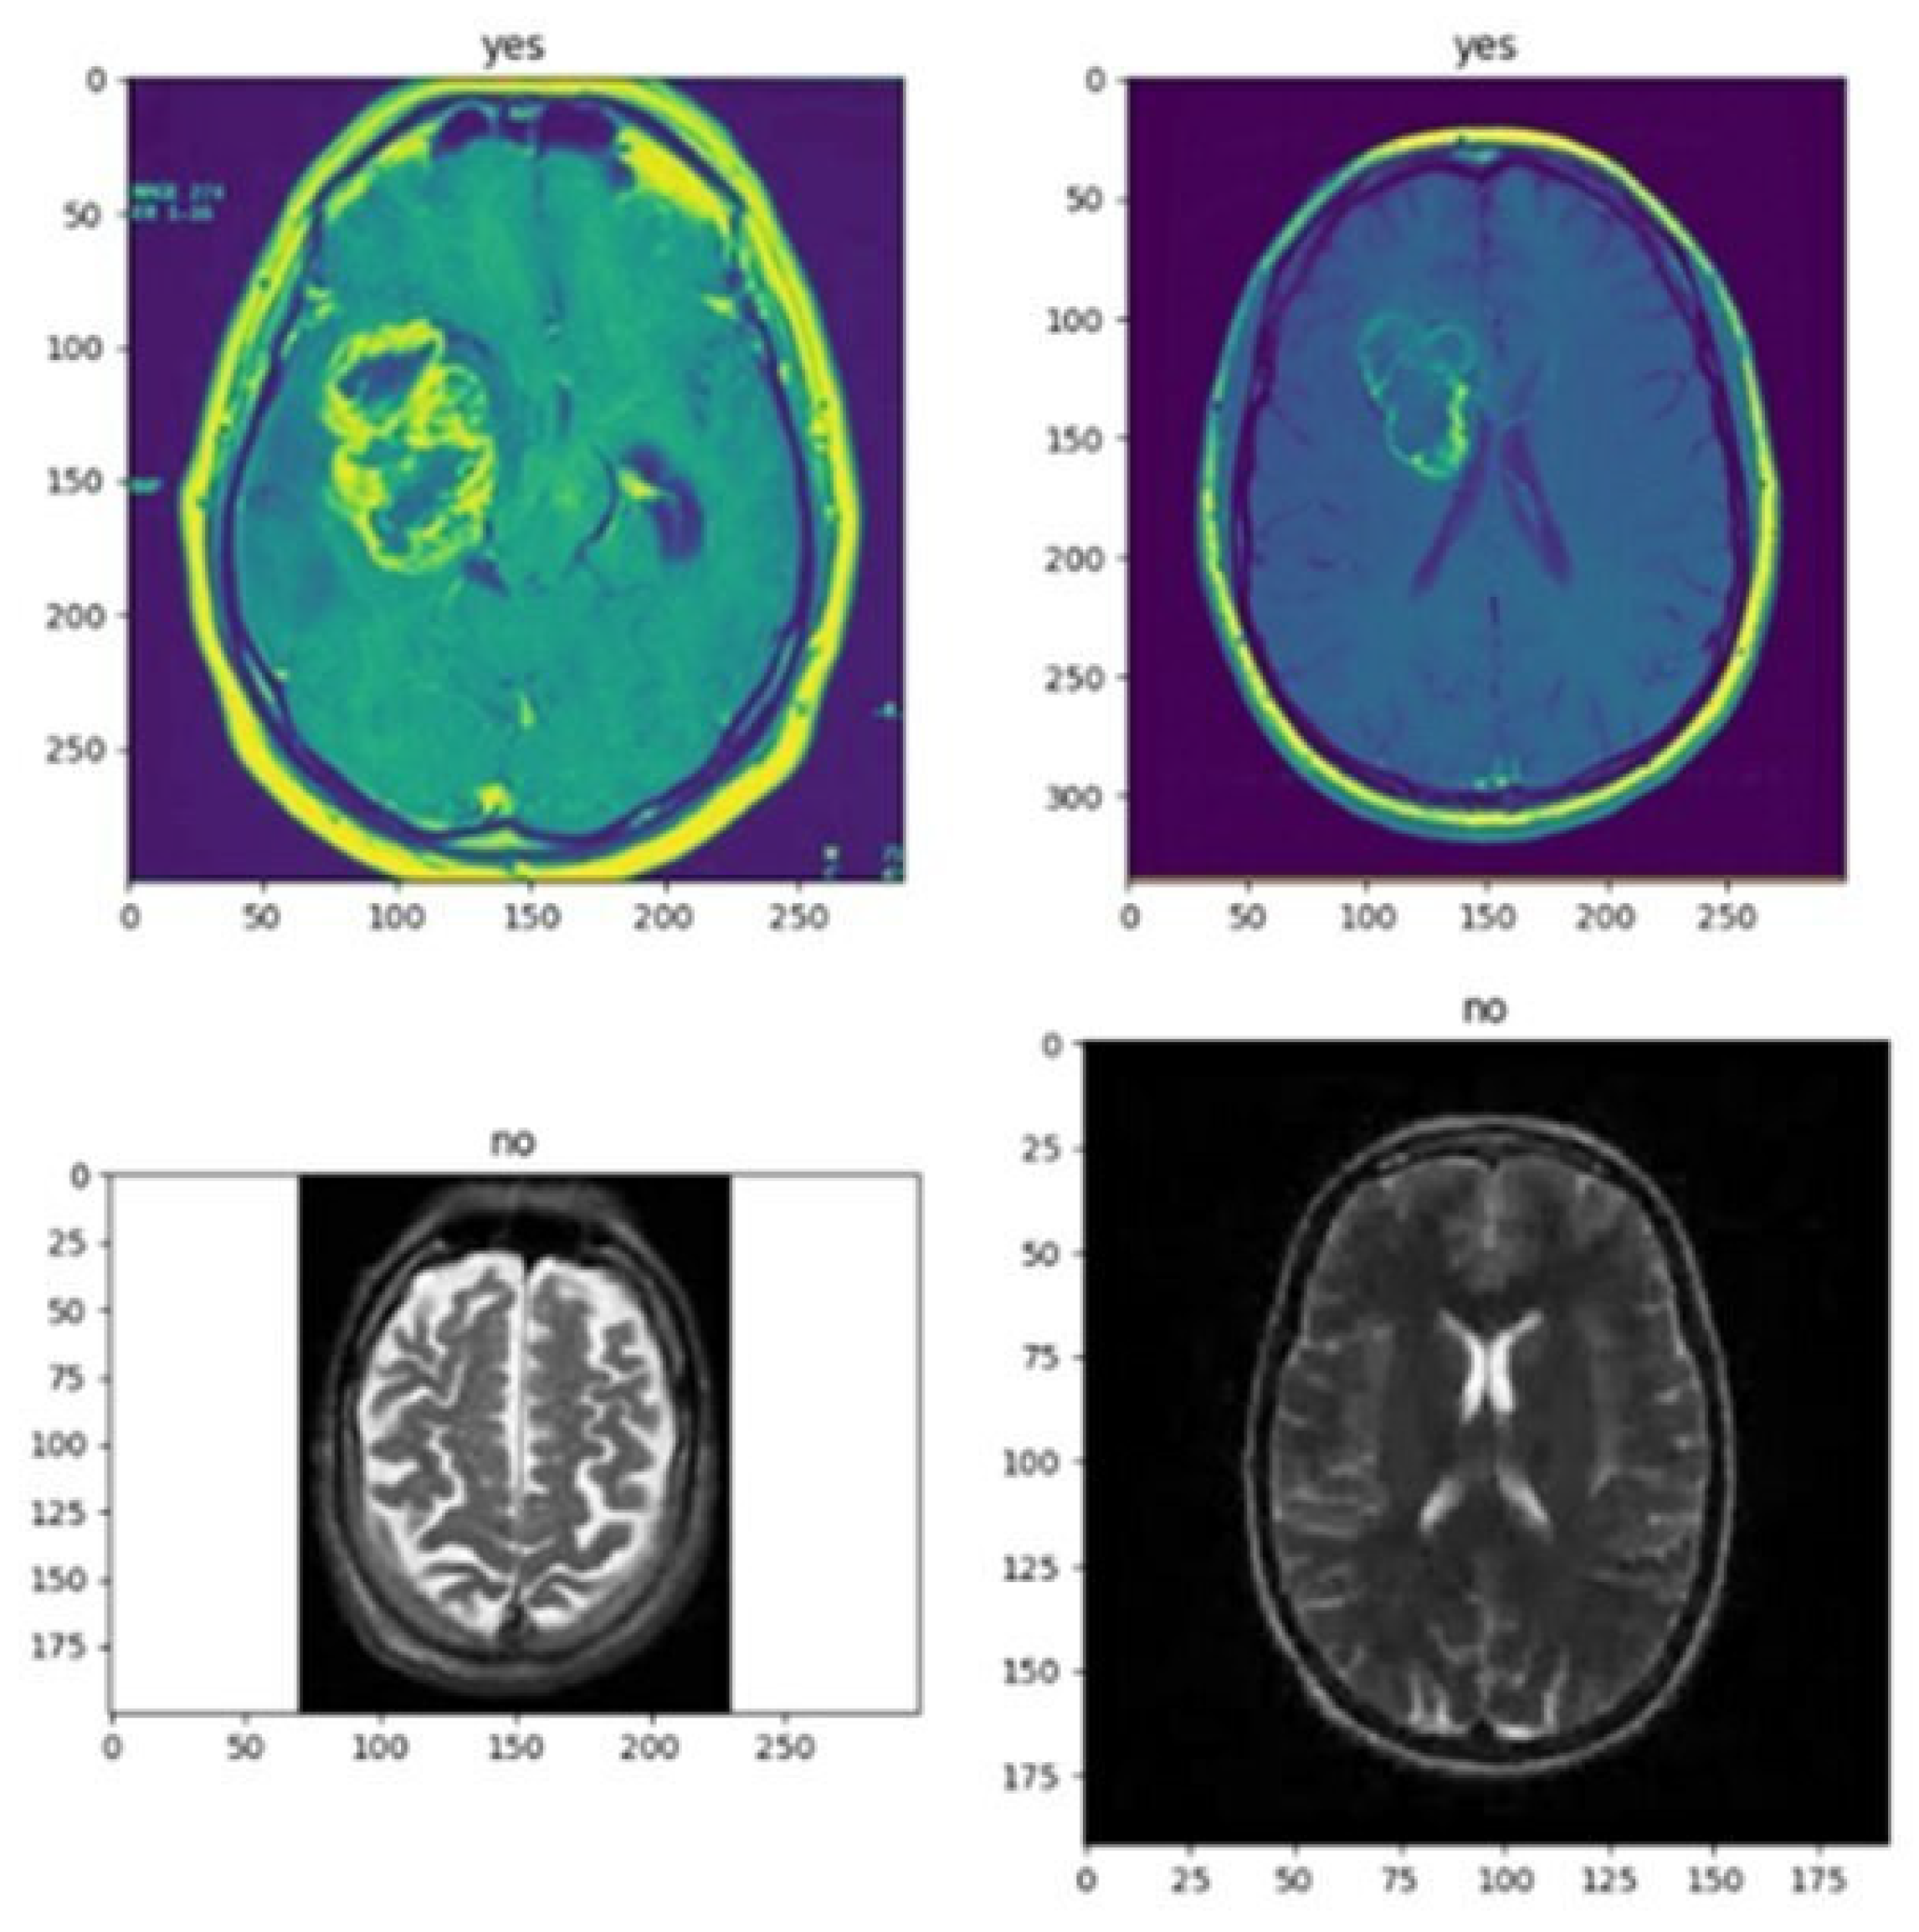

- Image Processing: There are many imaging techniques that use the brain, including Magnetic Resonance Imaging (MRI), Computed Tomography (CT), and Positron Emission Tomography (PET). Each model has its own strengths and limitations, and the choice of model will depend on the specific issue and capability. MRI is the most widely used for brain imaging. It has a high resolution and similar texture, making it ideal for determining the location and size of a tumor. MRI can also provide information about the blood supply to the tumor and the presence of enemas (swelling). MRI is noninvasive and contains no ionizing radiation, making it safe and versatile. However, MRI can be expensive and time-consuming, and patients may feel claustrophobic or uncomfortable during the scan. CT is another method that can be used to image brain tumors. It uses X-rays to create detailed images of the brain that can be used to determine the location and size of tumors. CT is faster, cheaper, and sometimes more effective than MRI. However, CT contains ionizing radiation, which can be dangerous to patients, and provides less contrast between soft tissues than MRI. PET is a technique that can be used to identify areas of the brain with increased metabolic activity that may indicate the presence of cancer. PET scans are often used with CT or MRI scans to give more details regarding the tumor’s dimensions and position. PET scans involve injections of antibodies that can be harmful to patients and are more expensive and more common than MRI or CT. For in-depth investigations, MRI is often preferred because of its high resolution and tissue homogeneity. MRI images can be used to create 3D volumes of the brain. They can be applied to deep learning model instructional design and evaluation. CT and PET images can also be used for in-depth investigations but may require additional pre-processing steps to improve image quality and reduce noise. In general, the choice of modality depends on the specific questions and available resources, but MRI is generally considered the gold standard for neuroimaging.

- Image Classification: In computer vision, classifying images is a frequent activity that entails labeling a picture according to its visual information. Image classification aims to create a model that can correctly recognize the objects or scenes that are seen in an image and give the image the appropriate label or labels.